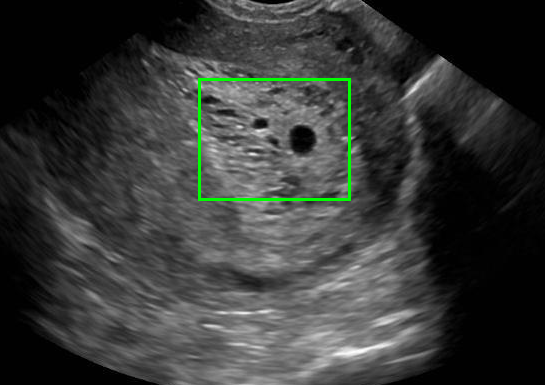

Example 2: restoration of images corrupted by blur and SPN or AWLN. In this example we evaluate the performance of the proposed TV-L1 model on three medical test images lungs (), Fig. 5 (a), ecography (), Fig. 6 (a), and aneurism (), Fig. 7 (a), synthetically corrupted by Gaussian blur of parameters band=5 and sigma=1 and by two types of impulsive noise, namely SPN and AWLN.

| (a) original | (b) TV-L1 (ISNR = 22.13) | (c) zoom of (b) |

![]() |

| (d) corrupted | (e) TVp-L1 (ISNR = 23.15) | (f) zoom of (e) |

| (g) -map () | (h) TV-L1 (ISNR = 25.46) | (i) zoom of (h) |

| (l) -map () | (m) TV-L1 (ISNR = 28.01) | (n) zoom of (m) |

First, for what concerns corruptions by SPN, in Figs. 5, 6, 7 we report for the three considered test images the original and corrupted image together with the estimated -maps in the first column (with the size of the neighborhoods used for the -maps estimation reported in the captions), the restoration results, obtained by the four compared methods, in the second column (with the achieved ISNR values in the captions) and a zoomed detail of the restored images - green- bordered in Figs. 5 (a), 6 (a), 7 (a) - in the last column.

The reported ISNR values as well as the visual inspection of the restored images and of the zoomed details strongly indicate how the proposed space-variant regularizer allows for higher quality restorations. In particular, it is worth remarking how, with respect to the space-variant TV model, the additional degrees of freedom represented by the scale parameters used in our proposal, yield a sufficient additional flexibility for avoiding unwanted spurious effects - see, e.g., spikes in Figs. 5 (i), 6 (i), 7 (i).